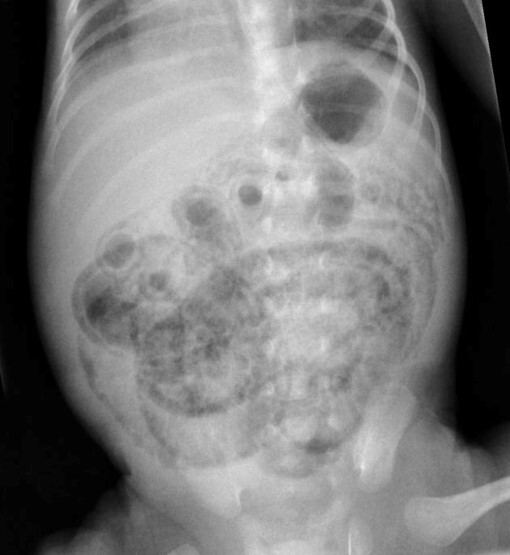

Cavernous hemangioma

Dilated blood vessels with stroma in-between the blood vessels that happens in the brain & liver

It doesn’t go away

What condition can cavernous hemangioma lead to

Von Hippel Lindau disease do a CT scan

How do you treat cavernous hemangioma

Ligating blood vessels

Describe the features of Von HIPPEL-Lindau syndrome

- Hemangioblastoma - Increased risk of renal cell carcinoma - Pheochromocytoma - Pancreatic lesions (cysts, cystadenomas, & neuroendocrine tumors) - Eye lesions (retinal angiomas or hemangioblastomas)

Describe the features of cavernous hemangiomas

- Found in blood vessels in the brain, lungs, and liver - Presents with neurological deficits (speech & memory loss) and problems & seizures - Need surgery to remove them